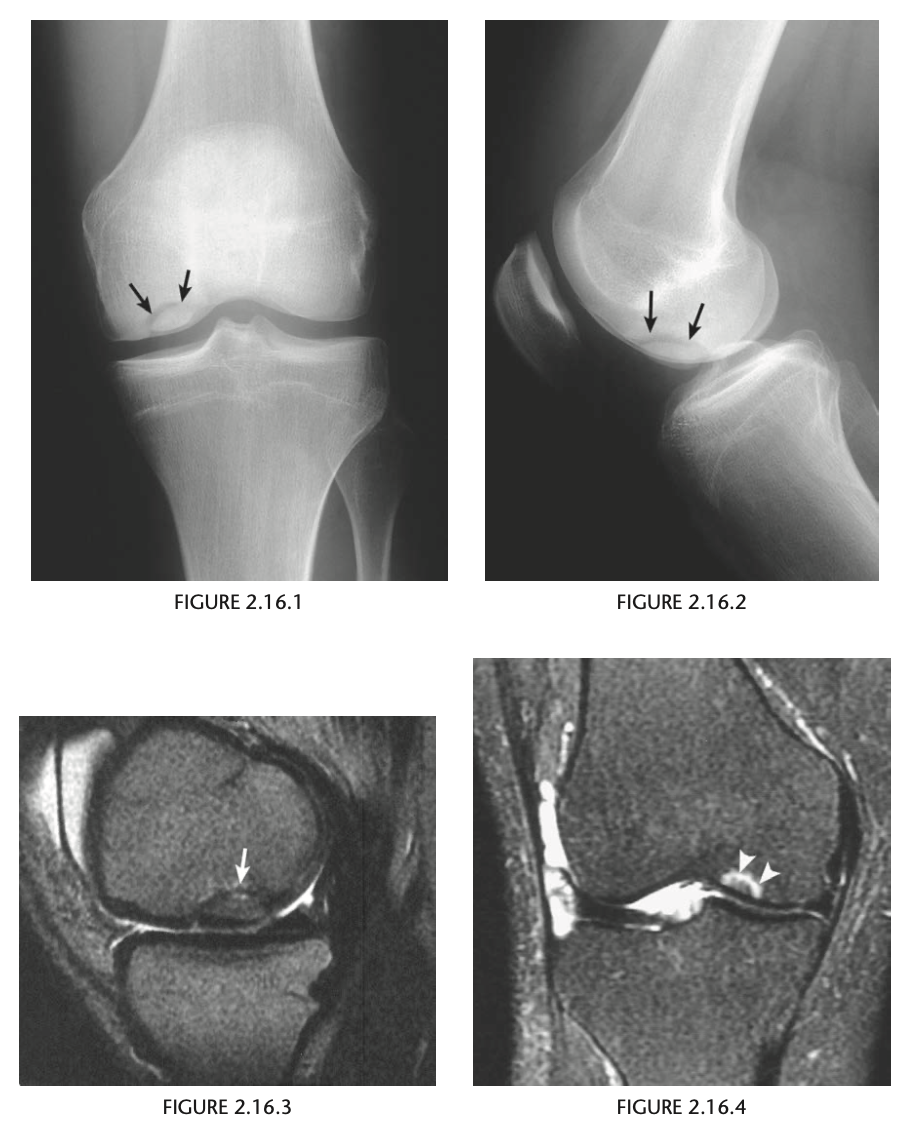

A 19-year-old man with pain in the left knee

Anteroposterior (Fig. 2.16.1) and lateral

(Fig. 2.16.2) radiographs of the left knee show a semi-

circular lucency, with an adjacent bony fragment,

on the lateral aspect of the medial femoral condyle

(arrows).

sagittal T2-weighted MR

image in the same patient demonstrates minimal

linear increased signal intensity in the same region

as the lucency, located between the subchondral

bone and the fragment (Fig. 2.16.3, arrow). The frag-

ment has low signal intensity and is not completely

covered by cartilage.

Osteochondritis dissecans (osteochon-

drosis) of the medial femoral condyle

from an osteochondral fracture

that was initially caused by shearing, rotatory, or

tangentially aligned impaction forces.

The presence of linear high T2-weighted

signal intensity between the fragment and donor site

indicates fluid or granulation tissue and strongly sug-

gests instability of the fragment (i.e., loose in situ

fragment) (Fig. 2.16.4, arrowheads). Focal cystic areas

beneath the fragment or denudation of articular carti-

lage are also MR signs suggesting an unstable fragment.

All patients with radiographic evidence of osteochon-

dritis dissecans could potentially benefit from MRI to

assess the integrity of the donor fragments before any

surgical or arthroscopic intervention or therapy (71).